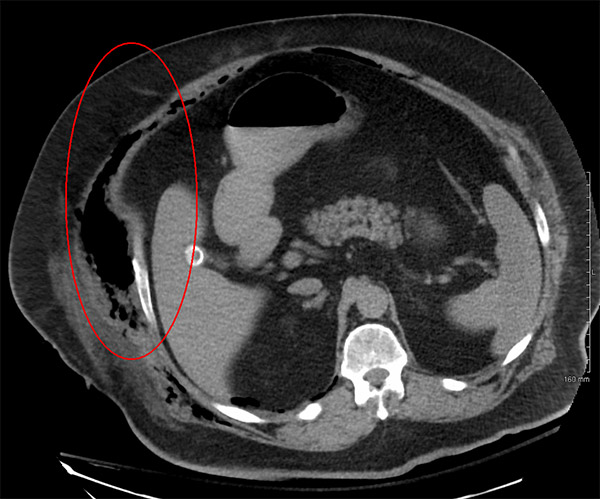

การวินิจฉัยโรค Necrotizing fasciitis

แพทย์จะวินิจฉัยอาการติดเชื้อโดยดูจากความรวดเร็วของอาการของโรคที่เริ่มเกิดขึ้นและความรวดเร็วในการลุกลาม เนื้อเยื่อที่ติดเชื้ออาจจะถูกตัดไปตรวจชนิดของแบคทีเรีย การตรวจเลือด มีการเอ็กซเรย์ ทำ CT scan หรือ MRI scan เพื่อดูอาการบาดเจ็บของอวัยวะหรือเพื่อดูว่าการกระจายของการติดเชื้อมีมากเพียงใด

ส่วนที่วงกลมแสดงช่องแก็สในเนื้อเยื่อที่เกิดจากเชื้อแบคทีเรีย